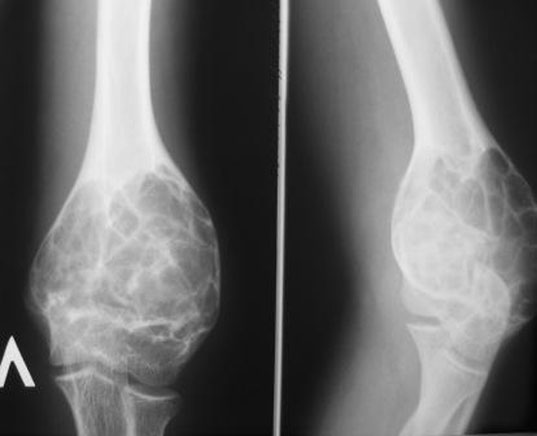

Рентгеновские снимки доброкачественных опухолей костей